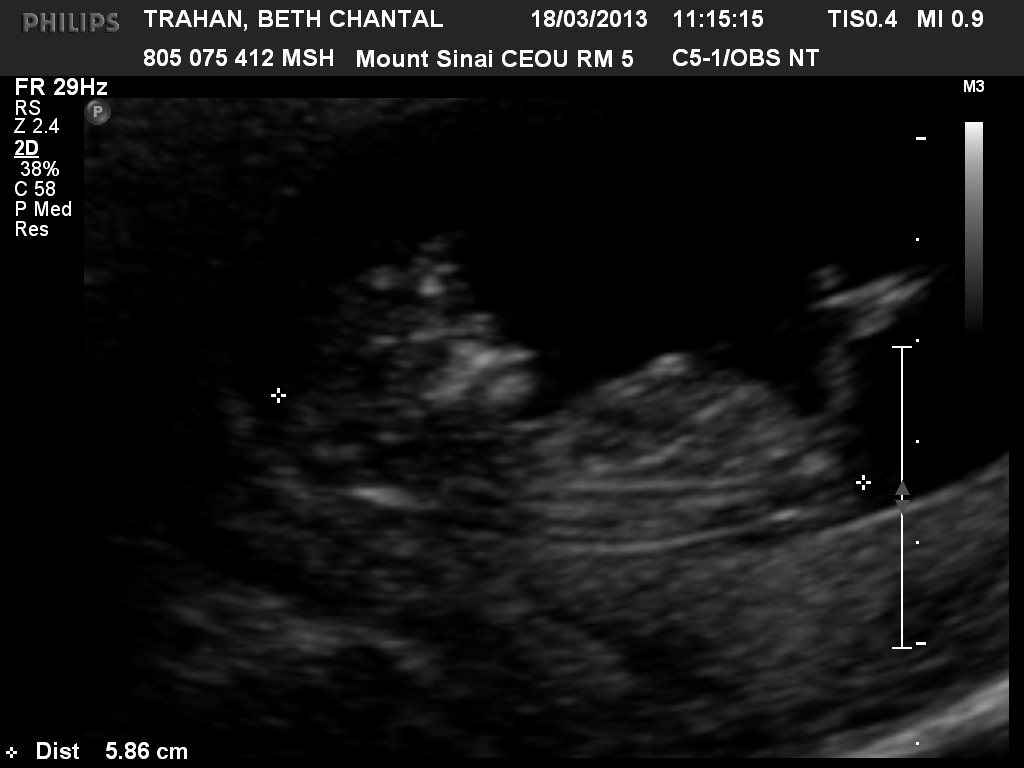

Attachment 9733Attachment 9732 can anyone tell what my bean may be i have 3 boys 1 girl i hope this time its a girl

12 weeks 6 days and thank you she's 12 and really wants a sister

Well Saturday I'm taking a drive to buffalo ny to find out I'm ontario Canada ill have to wait till may6 :( I'm to excited lol

Yay it's a girl